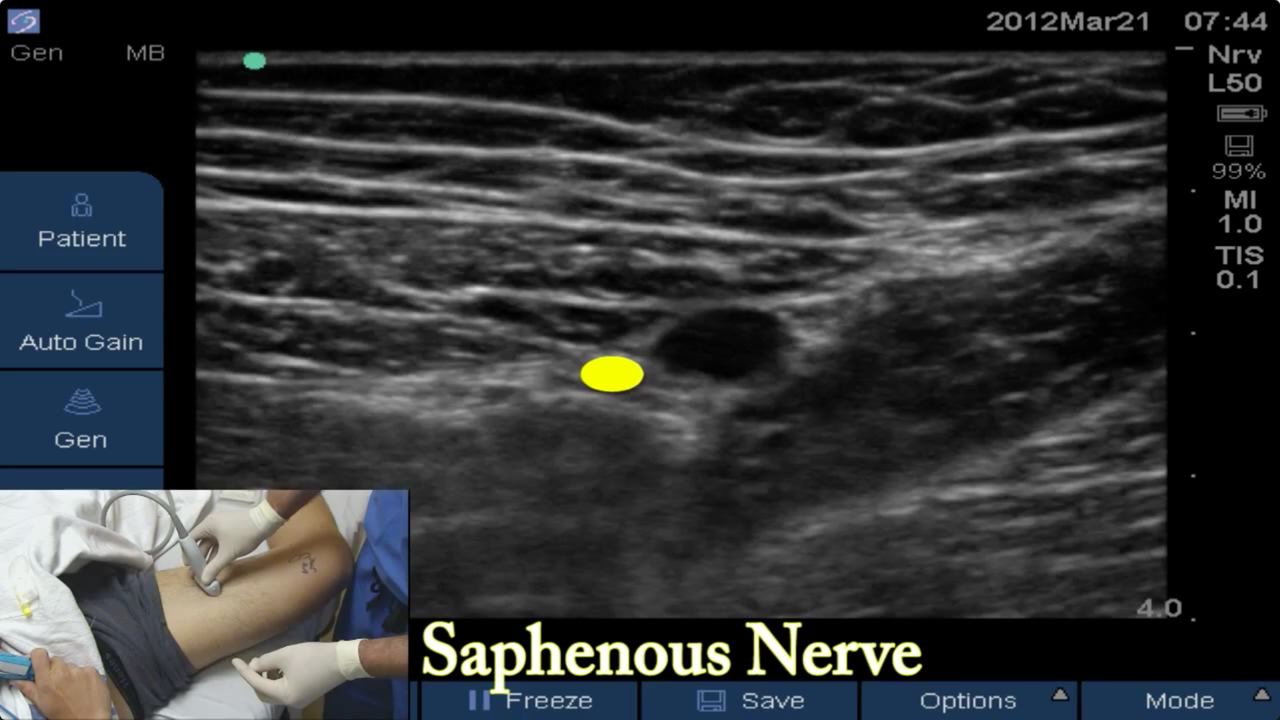

• US-Guided Rescue Mid-thigh Saphenous Block in the Adductor Canal

Brandon Winchester performs a rescue adductor canal block in the mid-thigh to block the saphenous (medial) component of postoperative pain following an ankle arthroscopy.